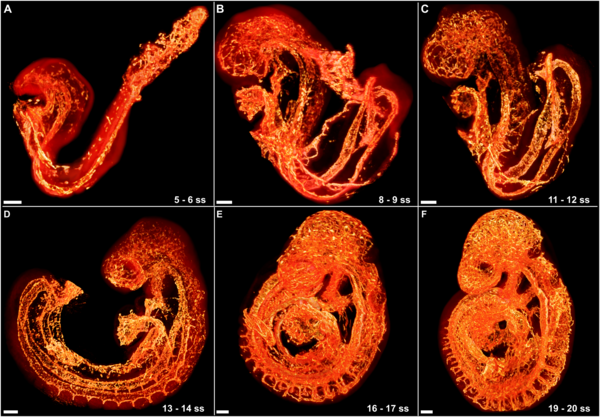

১. ‘আলাকাহ’ — জোঁকের মতো ঝুলে থাকা পদার্থ

কোরআন:

“তিনি মানুষকে সৃষ্টি করেছেন জমাটবাঁধা রক্তপিণ্ড (আলাকাহ) থেকে।”

— (সূরা আলাক: ২)

আলাকাহ শব্দের তিনটি অর্থ:

- জোঁকের মতো আকৃতি

- ঝুলে থাকা বস্তু

- জমাট রক্ত বা লেগে থাকা পদার্থ

ড. কিথ মূর মাইক্রোস্কোপে মানুষের প্রাথমিক ভ্রূণ দেখেন ও জোঁকের ছবির সঙ্গে তুলনা করে হুবহু মিল পান—

✔ আকার

✔ লেগে থাকা

✔ পুষ্টি শোষণের ধরন

এটি সপ্তম শতকের আরব বিশ্বের জ্ঞানের অনেক বাইরে ছিল।